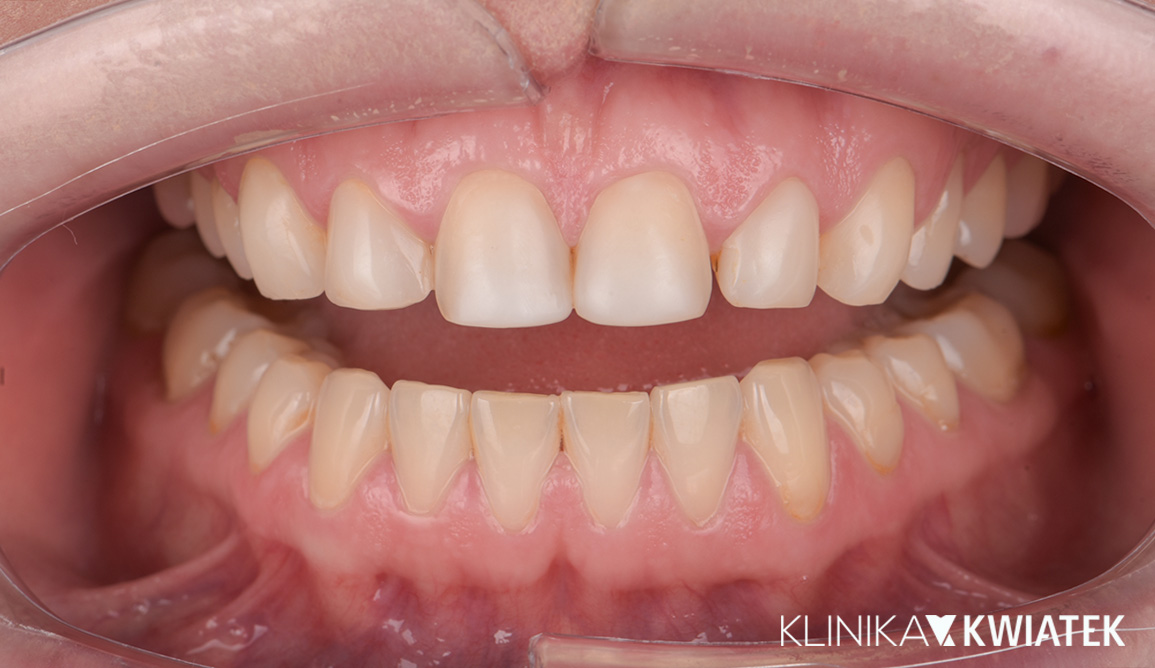

Kompleksowa transformacja uśmiechu po leczeniu ortodontycznym

Pacjentka zgłosiła się do kliniki po zakończeniu leczenia ortodontycznego nakładkami w innym gabinecie, w celu odbudowy brakującego zęba trzonowego. Po szczegółowej diagnostyce zaplanowano leczenie implantologiczne, protetyczne oraz periodontologiczne. Dzięki precyzyjnej pracy zespołu specjalistów uzyskano pełną odbudowę estetyki i funkcji – naturalny, harmonijny uśmiech oraz zdrowe, stabilne przyzębie.